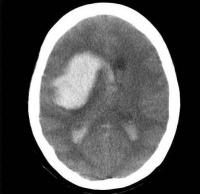

(二)脑出血(cerebral hemorrhage) 是指原发于脑实质内血管破裂引起的出血

脑出血

出现典型的上运动神经元性瘫痪,患者有高血压动脉粥样硬化病史,以55岁以上中老年人居多,多在动态和用力状态下发病。出现前数小时至数日常有头痛眩晕意识混浊的先兆症状。起病急,进展快,常出现意识障碍、偏瘫、早期呕吐和其他神经系统局灶症状。脑脊液压力增高,80%脑脊液中混有血液,50%患者呈血性外观,CT检查可见颅内血肿高密度阴影。